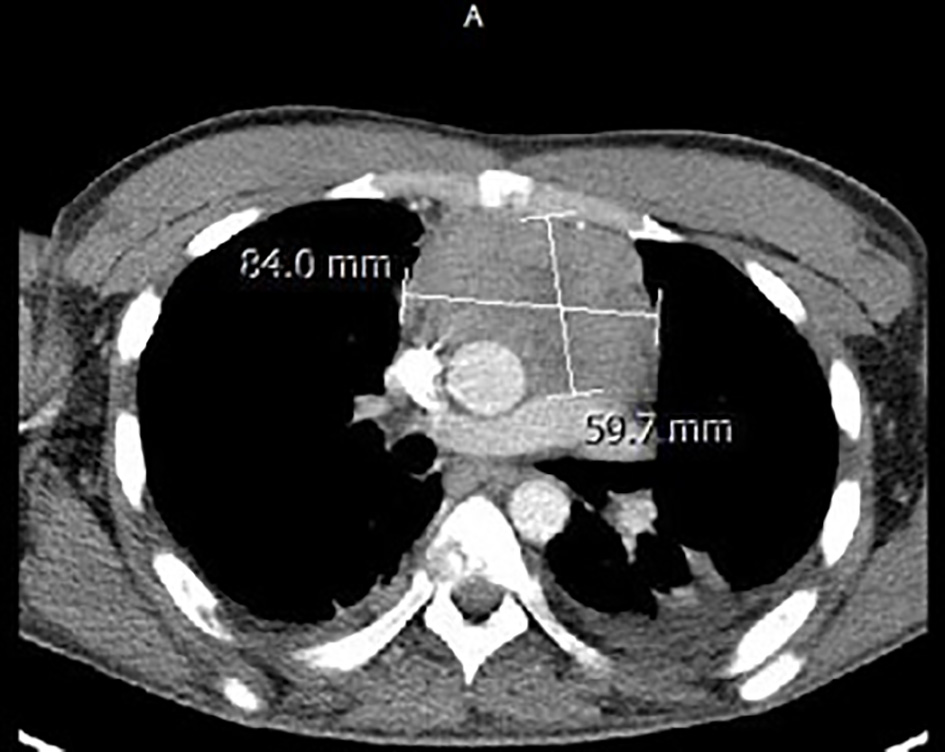

Magnetic resonance imaging (MRI) of the spine reported an epidural mass at T12-L1 level with spinal canal stenosis at T12 level (Fig. 1). Further workup included CT of chest/abdomen and pelvis which showed a large anterior mediastinal mass measuring 8.4 × 5.9 cm (Fig. 2), mixed lytic/sclerotic bony lesions in the spinal bodies from T10 to L1 (Fig. 3), the iliac crests, left sacrum, and the left ischial tuberosity and left supraclavicular lymphadenopathy (Fig. 4). The differential at that time inclined towards germ cell tumor and lymphoma and decision was made to biopsy the left supraclavicular fossa lymph node.

Figure 2. Computed tomogram of the chest depicting the large anterior mediastinal mass.